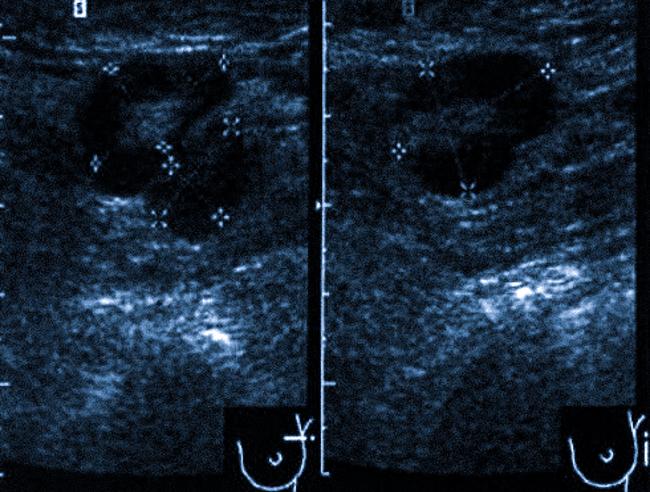

Метастазы рака молочной железы в поверхностные лимфоузлы

Кроме диагностики причин впервые возникшей аденопатии, УЗИ также используется у онкологических больных как метод скрининга. Сканирование лимфатических узлов у этих пациентов должно проводиться после оперативного вмешательства и/или химиотерапии не реже одного раза в год.

Ценность эхографии в медицине заключается и в возможности проведения неинвазивной пункции лимфатических узлов. Под УЗ-контролем врач с помощью тонкой иглы получает содержимое анатомического образования (аспирационная биопсия) и направляет материал в лабораторию. По результатам микроскопического анализа определяют характер и природу патологического процесса.

Для определения сторожевого узла при раке молочной железы используется аксиллография, так как пальпация не позволяет выявить метастатические лимфоузлы внутри самой железы даже опытному врачу. Аксиллография (рентгенологическое исследование лимфатических узлов) помогает установить первичность или вторичность опухолевого процесса, что, в свою очередь, позволяет сделать прогноз.

Как лимфоузлы с жировой дистрофией исследуются в медицинской практике?

Для диагностики жировой дистрофии лимфоузлов используются различные методы визуализации, такие как ультразвуковое исследование (УЗИ), компьютерная томография (КТ) и магнитно-резонансная томография (МРТ). Эти методы позволяют оценить размер, структуру и состояние лимфоузлов. В некоторых случаях может потребоваться биопсия для гистологического исследования, что поможет не только подтвердить наличие жировой дистрофии, но и исключить или подтвердить другие серьезные заболевания. Важно, чтобы диагностика проводилась квалифицированным специалистом, чтобы правильно интерпретировать результаты и определить дальнейшие шаги в лечении.